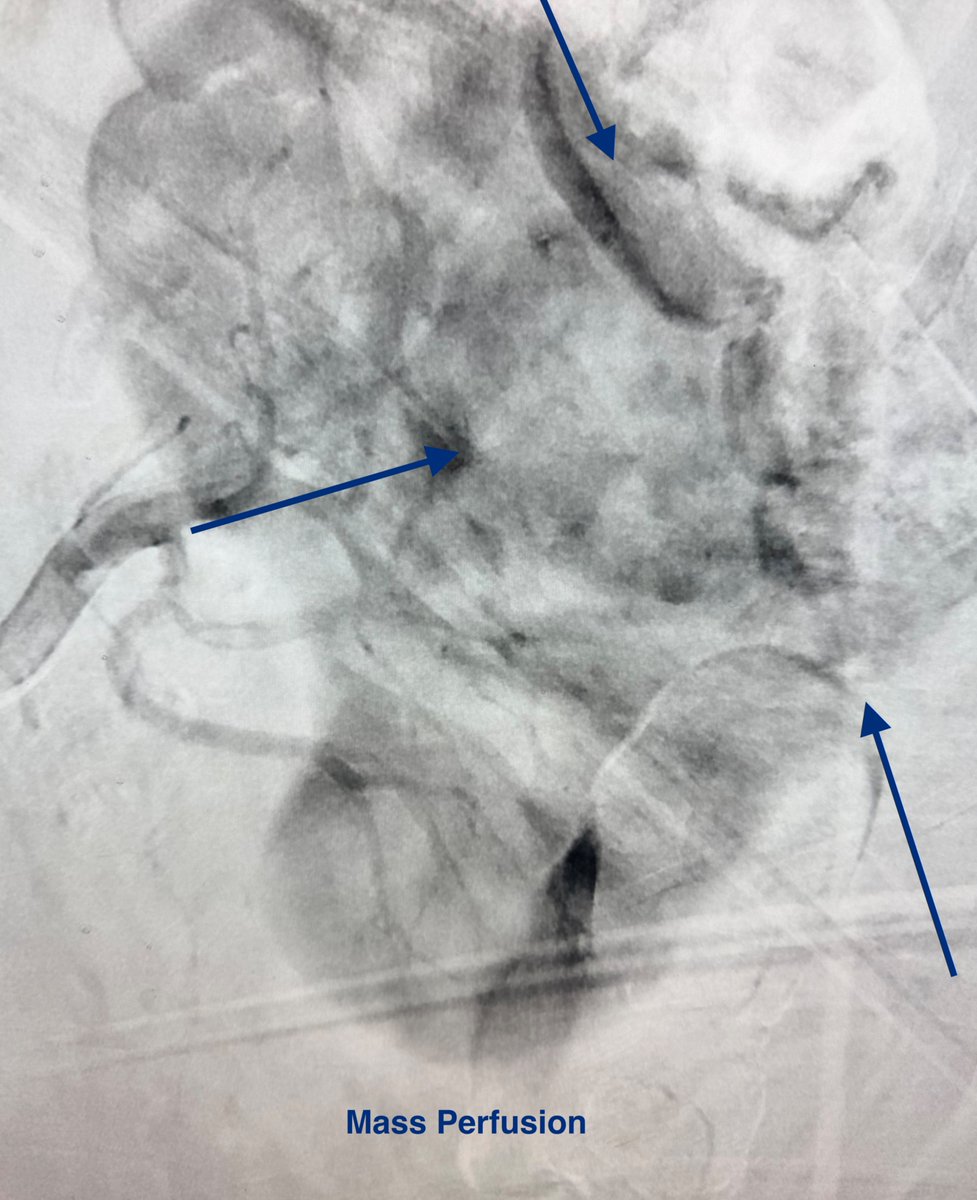

A unique use of HDR! High-risk saddle PE (now called stage D), in a patient with baseline cardiac index 1.2. Cleared out all right lung except the lower branch (full of clots), attempts to wire or manipulate the penumbra catheter in the branch failed. So I borrowed the coronary #CTO #PCI technique, engaged the cap with the Select catheter. Some contrast to stain, then "wired" the branch with the catheter over which I used the @PenVascular catheter to clean the branch! I think coronary CTO operators can have a solution for any vascular bed! #CardioX